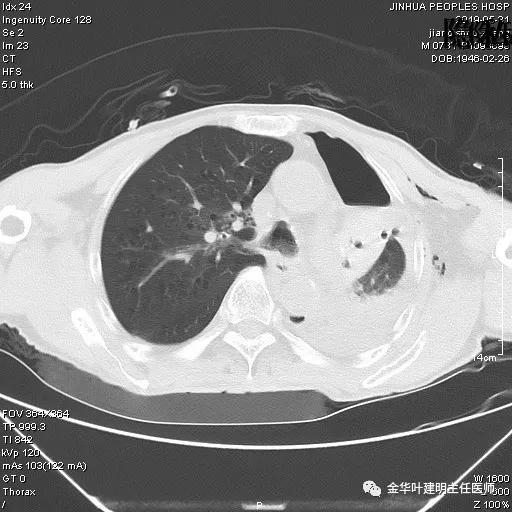

考虑左侧大量胸腔积液,遂进一步胸部CT检查:

以上是肺窗表现,下面为纵隔窗影像: